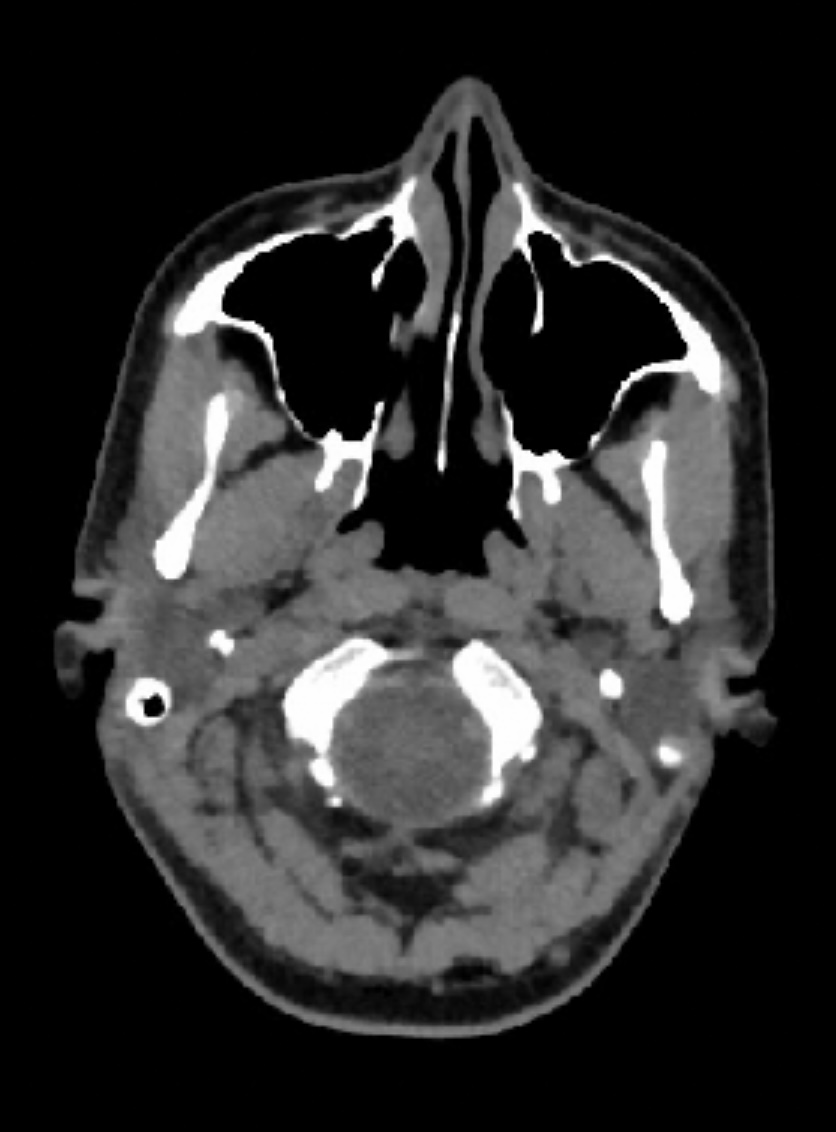

@jrhode2873 axial view is the best to see the IJV compression. If you go to the axial view, look for C1. I’ve attached my own imaging to help you find it. It’s the vertebrae that has wings!

It’s often hard to tell if the styloids are at play with IJV compression in the 3D models. Sometimes it just ends up being C1 causing the compression, but can never know for sure unless I see the axial view!

There may or may not be depending on length. That’s why the axial view is beneficial. If you find your C1 in the axial view like I showed above, I can help you look at compression